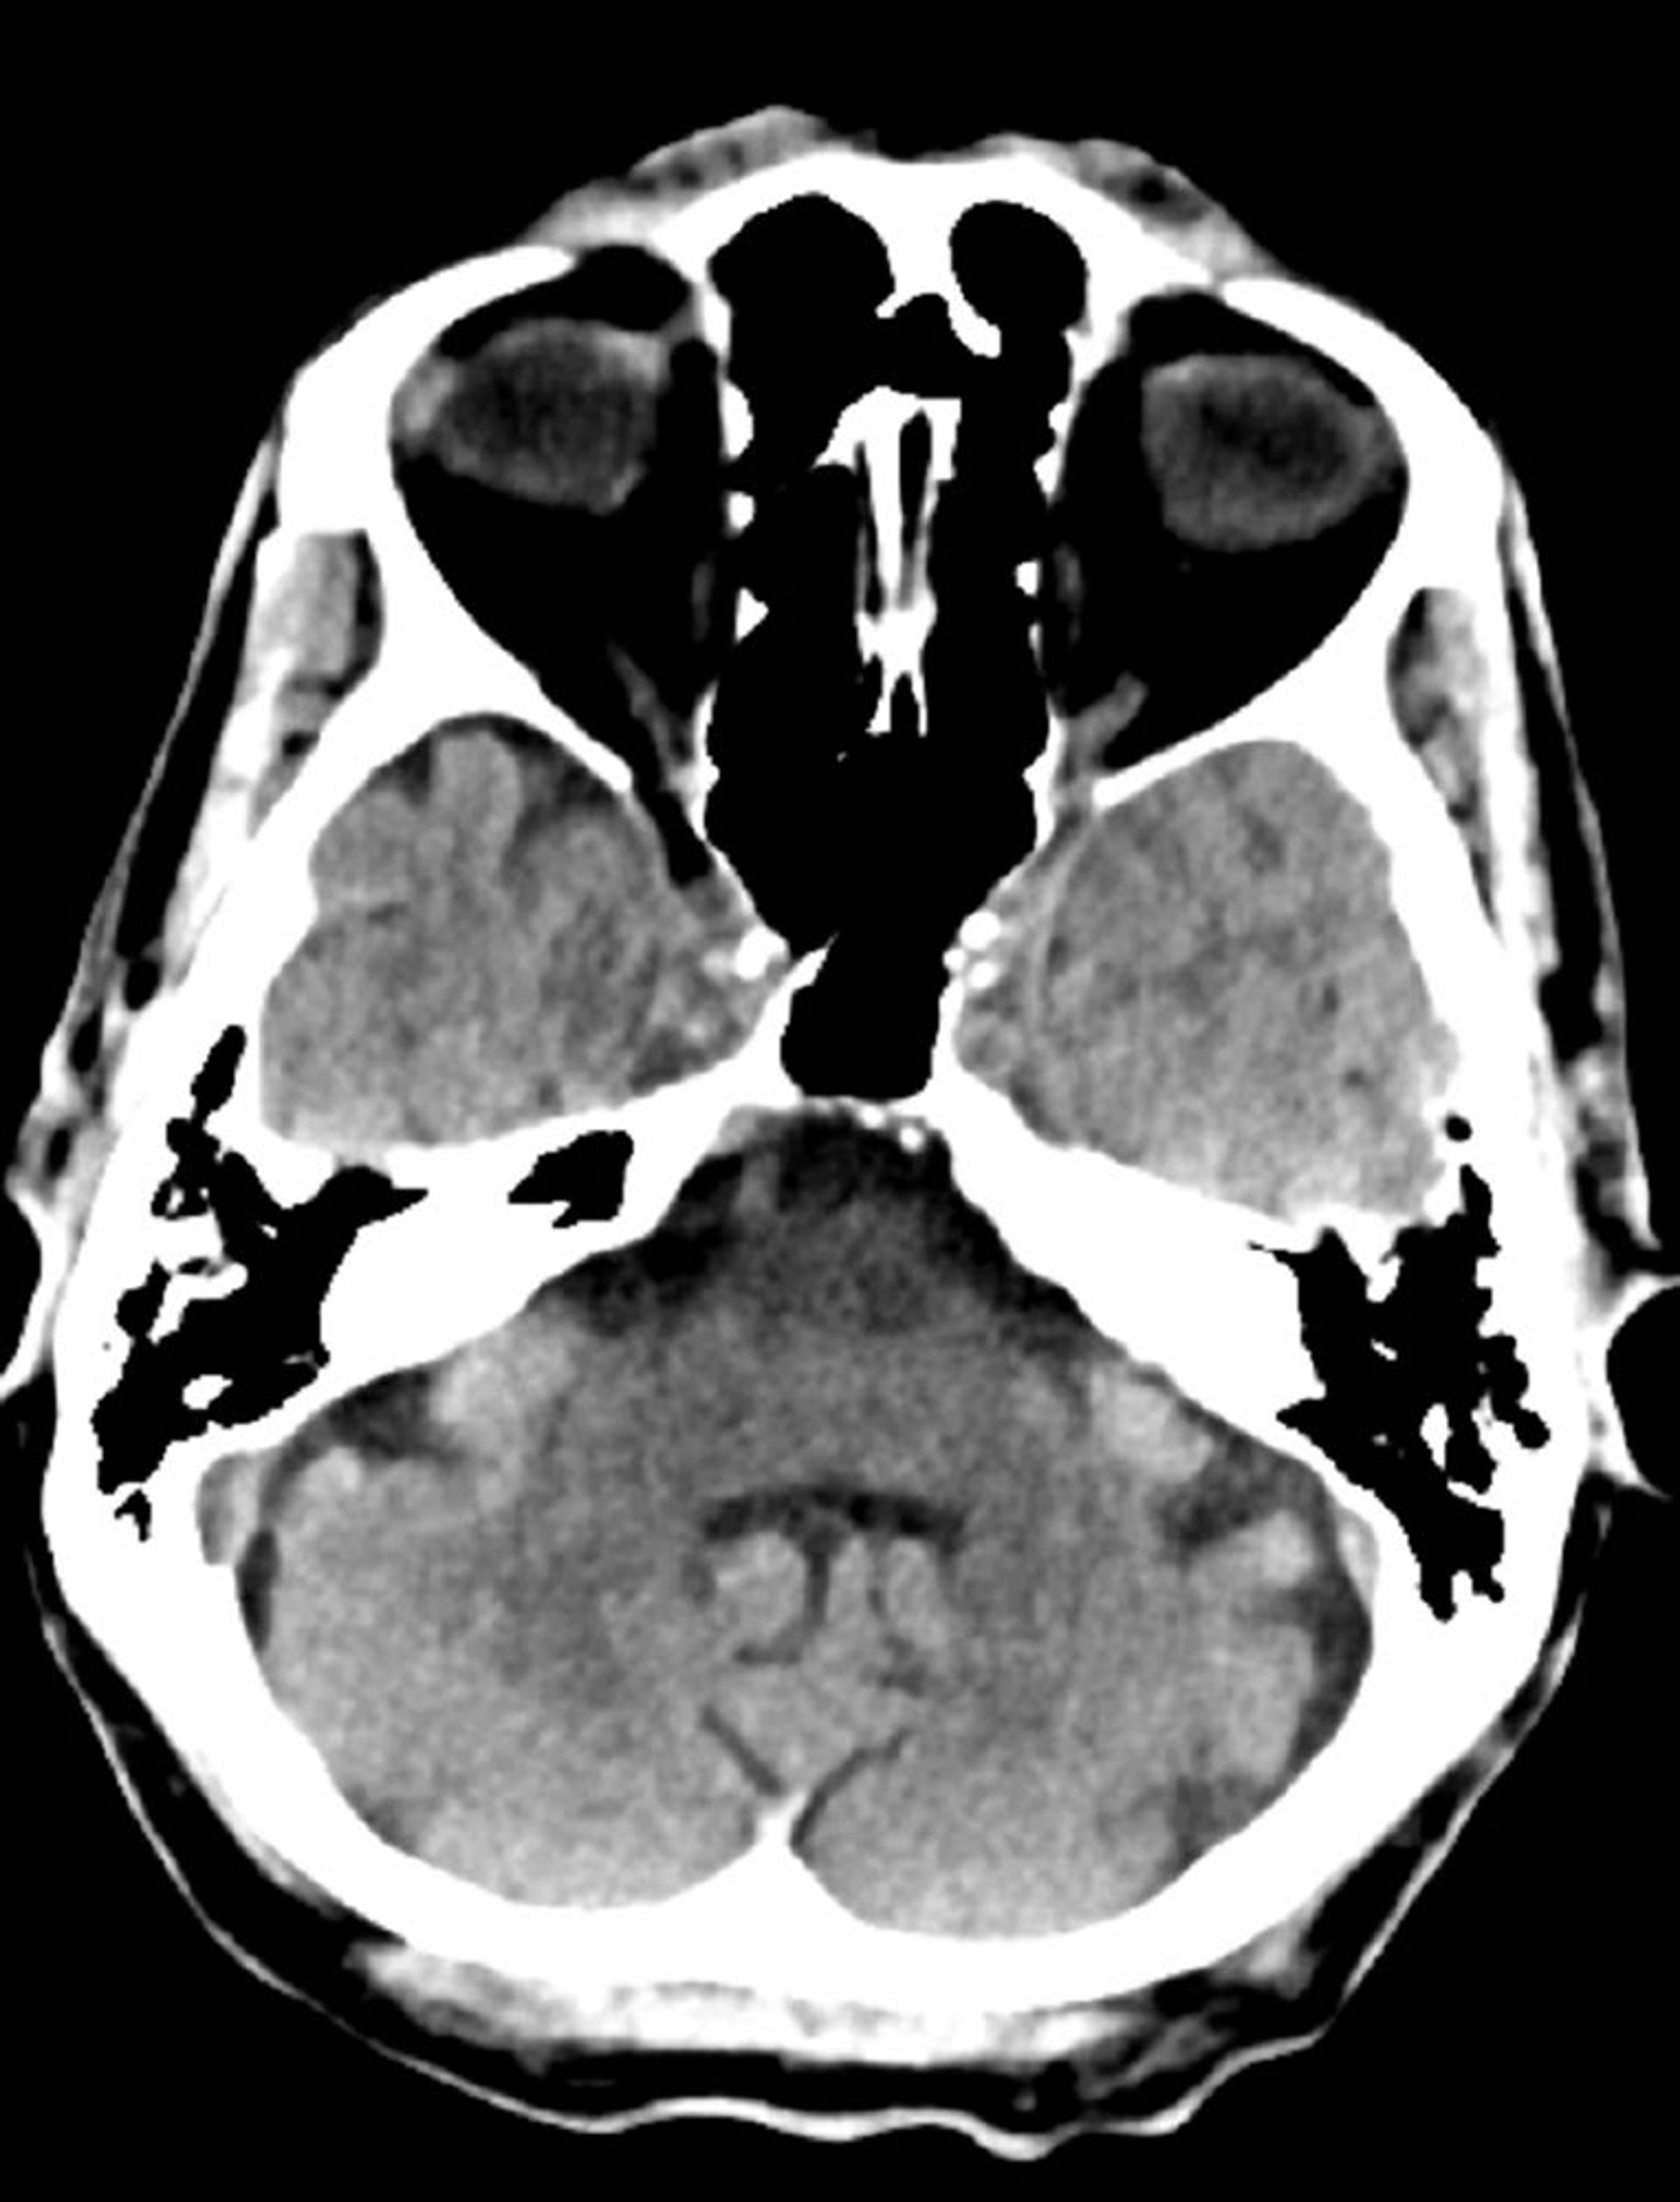

Chụp CT đầu bình thường (người lớn, 74 tuổi) – Lát cắt 8

Hình ảnh này là hình ảnh chụp CT đầu bình thường của một người lớn 74 tuổi. Khi so sánh với chụp CT đầu của một người 30 tuổi bình thường, các não thất và các khe lớn hơn. Những dấu hiệu này là bình thường ở nhóm tuổi này.